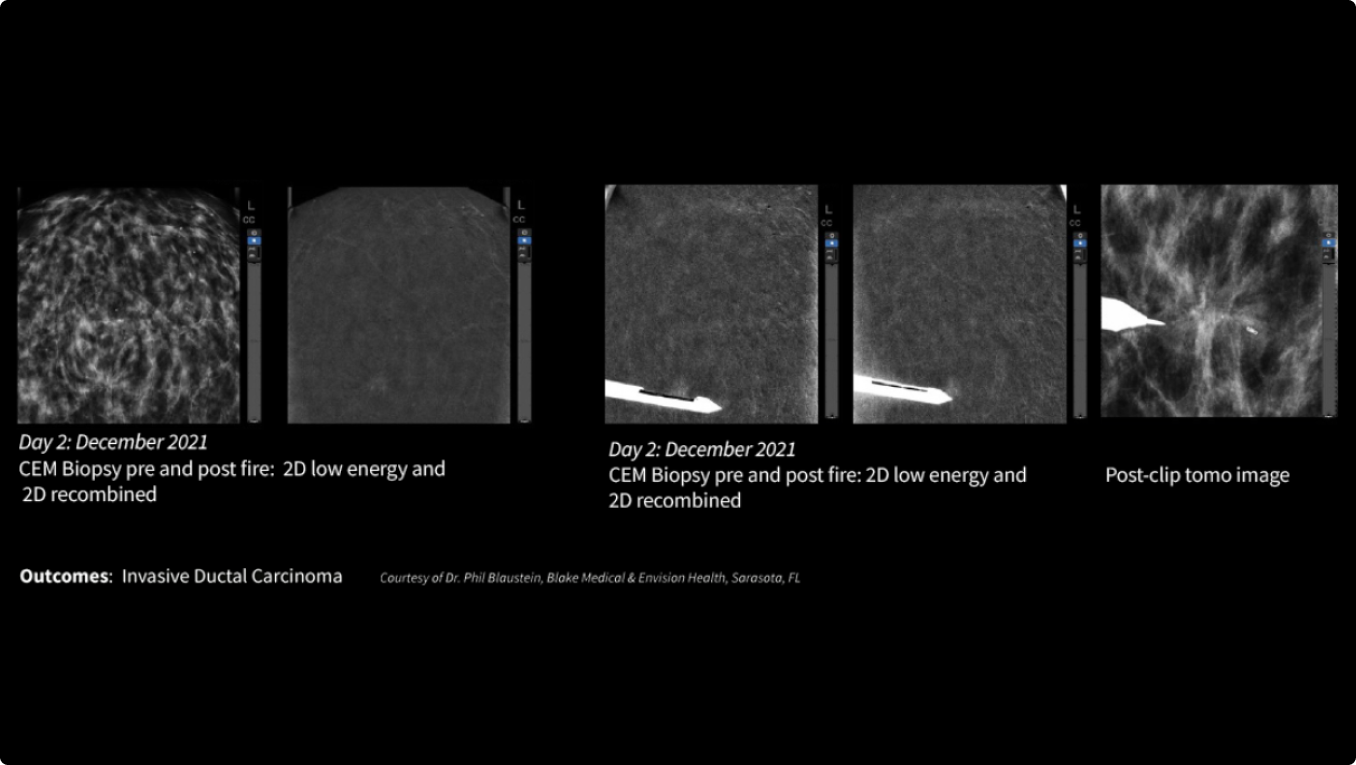

SEE AND BIOPSY WHAT MATTERS

Serena Bright™

Contrast-guided biopsy solution

Utilizes contrast-spectral mammography to clearly target and biopsy lesions without leaving the mammography suite.